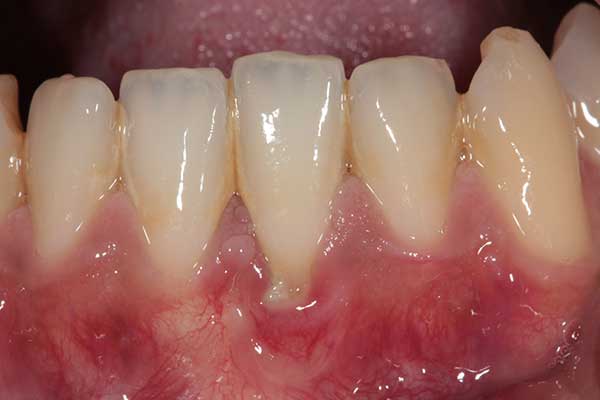

Según la Biblioteca Nacional de Medicina del Instituto de Salud de EE.UU, más del 37% de los jóvenes y adultos tiene retracción de las encías o recesión gingival, de este porcentaje, hasta un 9% de los dientes se ve afectado. Esta patología se describe como el retraimiento del tejido de la encía, quedando expuesta la raíz provocando una serie de problemas periodontales.

Además, otros factores que originan este problema dental son: bruxismo, mal posición de los dientes, infección, piercing lingual, frenillo lingual corto, encías muy delgadas, malos hábitos como comerse las uñas, entre otros, además de la genética y la edad que son determinantes. En relación a esto último y según el mismo estudio, el 90% de los adultos mayores presenta esta patología, donde hasta 56% de los dientes se ven afectados.

¿Cuáles son las consecuencias? El doctor Mitrano nos aclara que principalmente hay mayor sensibilidad y dolor, pero también problemas estéticos y de higiene, ya que hay que limpiarse los dientes desde más arriba, por lo tanto, si se no se hace correctamente puede haber un aumento de caries y de infección gingival.